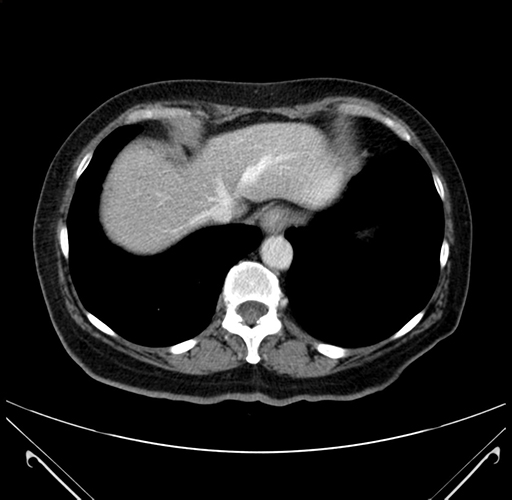

MRI T1